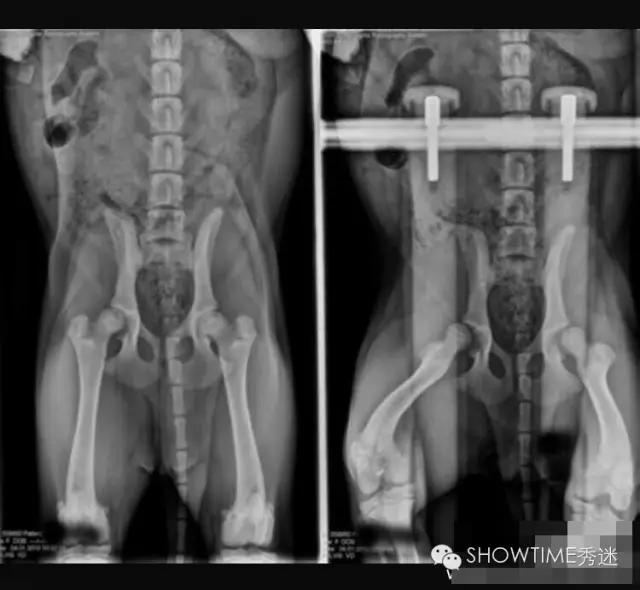

对于髋关节发育不良的判定,犬类骨科疾病种类很多,并非所有走路摇摆外八或者无力都是CHD。OFA组织是根据X光片来进行判断的,在犬只年满24月龄以后才会给出评判结果,24个月之前只做评估不做判定。因为犬在两岁前还在发育,股骨头和髋臼常会出现发育速度不一而产生髋关节发育不全的现象,这其中还要受到肌肉的影响。并且也有幼犬时期髋关节发育正常,而后随着成长过程发生严重变化,进而产生CHD症状,因此判定:只有在24月龄之后才能够做出。这是在美国和全世界至今应用最为广泛的方法,也是美国繁殖者在繁殖中的主要依托。

在髋关节发育不良的诊断中有一个最为重要的因素,就是X光片的拍摄要求。在国内很多医院因此而产生的误诊不胜枚举。